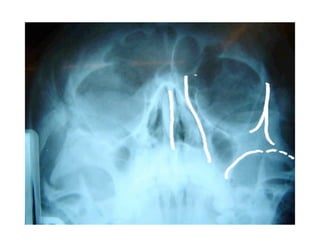

Este documento describe los principios de construcción de la arquitectura craneofacial, incluyendo el metamerismo, la simetría y la paquimería. Explica la organización peri-cavitaria del cráneo a través de columnas y vigas, y analiza las diferentes fascias profundas del cuello. También destaca la importancia de conocer la irrigación ósea con orientación quirúrgica, mencionando los principales aportes vasculares y suplementarios así como el origen, trayecto y retorno venoso de la carót